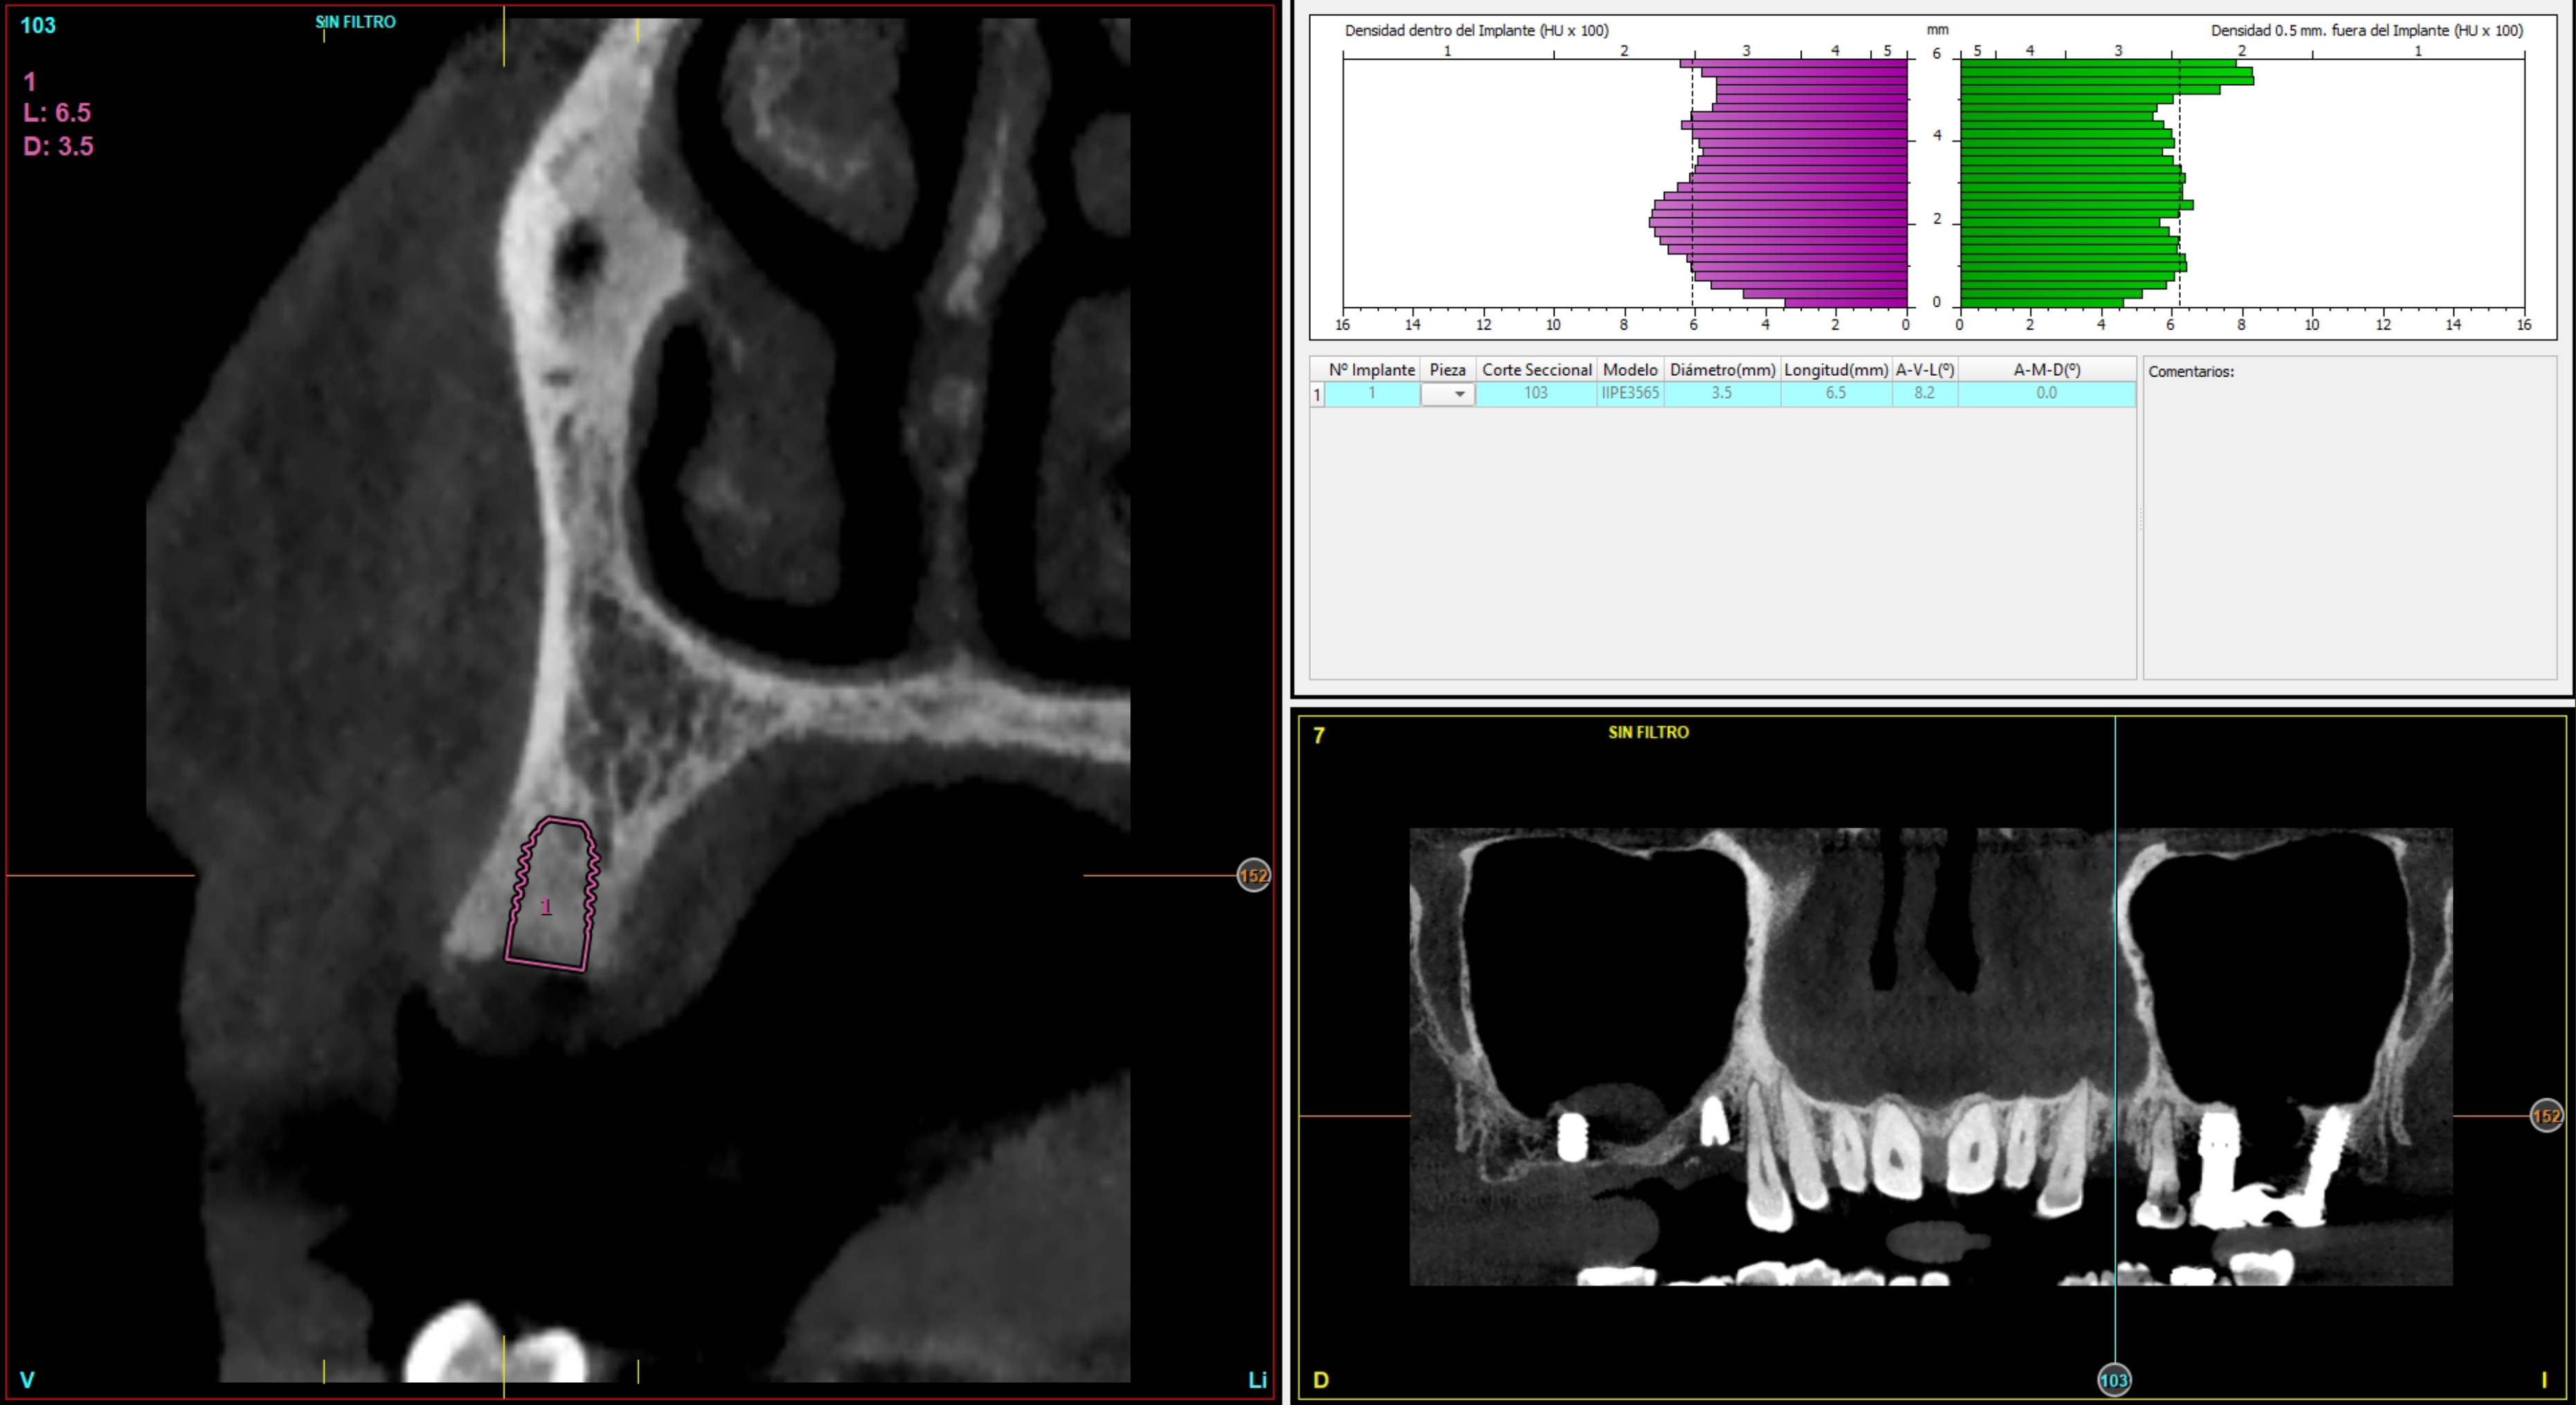

La pianificazione preoperatoria virtuale ha incluso la scansione intraorale e la CBCT. Con i dati raccolti sono stati generati modelli virtuali altamente precisi dell’anatomia del paziente ed è stata pianificata la posizione ideale degli impianti. In base a questa pianificazione sono state prodotte dime chirurgiche CAD/CAM per replicare la posizione e l’angolazione implantare pianificate. Le dime sono state fatte calzare sui denti adiacenti, incorporando i driver statici coerenti con il manipolo chirurgico utilizzato dall’operatore (Figura 1).

Grazie a dima e drivers, la chirurgia guidata consente una fresatura biologicamente incrementale come con un protocollo convenzionale; l’osso autologo raccolto durante la fresatura può essere utilizzato come particolato da innesto al bisogno. I dati clinici e demografici raccolti includono età, sesso, storia clinica e terapie farmacologiche in atto. I dati correlati agli impianti includono, invece, localizzazione anatomica, diametro, lunghezza, torque di inserzione, tipo di protesi, e parametri ossei rilevati alla diagnosi (Figure 2-3). Nel corso del follow-up sono stati registrati la sopravvivenza implantare protesica e il livello di osso marginale. I dati sono stati registrati da un esaminatore indipendente.

Le OPT a posizionamento del paziente standardizzato sono state eseguite alla consegna della protesi (3 mesi per la mandibola, 6 mesi per la maxilla) e a 1,3, 6 e 12 mesi dopo il carico. Le radiografie sono state calibrate con ImageJ utilizzando l’impianto di lunghezza conosciuta per correggere la magnificazione, mentre la perdita d’osso marginale è stata misurata dalla spalla dell’impianto al primo punto di contatto tra osso e impianto. Il dato principale è la perdita di osso marginale mesiale e distale; i dati secondari sono invece la sopravvivenza degli impianti e le complicazioni chirurgiche/protesiche. Il test di Shapiro-Wilk verifica la normalità; le variabili qualitative sono riassunte in base alla frequenza, mentre le variabili quantitative in base a media e deviazione standard. La sopravvivenza è analizzata con lo stimatore di Kaplan-Meier utilizzando il software SPSS v15.0 (Statistical Package for Social Science versione 15.0).

Il 20% degli impianti è stato posizionato nella mandibola (per lo più in posizione 47) e il restante 80% nel mascellare superiore (il 20% in posizione 16 e il 20% in posizione 25). Gli impianti posizionati nel mascellare superiore hanno trovato un osso tipo IV, mentre gli impianti posizionati nella mandibola hanno trovato un osso tipo III. Gli impianti utilizzati hanno un diametro compreso tra 4.0 e 4,5 mm (il 66.7% sono da 4.0 mm) e una lunghezza compresa tra 4.5 mm e 7.5 mm (il 53.3% sono lunghi 7.5 mm). Nell’86.7% dei casi non è stato eseguito alcun procedimento chirurgico aggiuntivo; in un caso, due impianti hanno previsto in rialzo di seno transcrestale con PRGF-Endoret e osso autologo. Nel 93.3% dei casi la protesizzazione ha previsto ponti avvitati a più elementi; un impianto è stato protesizzato mediante elemento singolo avvitato con componente transepiteliale. Il follow-up medio è stato di 12.4 ± 1.05 mesi dal carico. Il 100% degli impianti è sopravvissuto, senza complicanze né chirurgiche né protesiche. La perdita di osso media a 12 mesi è stata mesialmente di 0.15 ± 0.74 mm e distalmente di 0.13 ± 0.85 mm. La Figura 4 mostra l’osso perso su un singolo impianto e le Figure 5-14 illustrano un caso clinico rappresentativo.